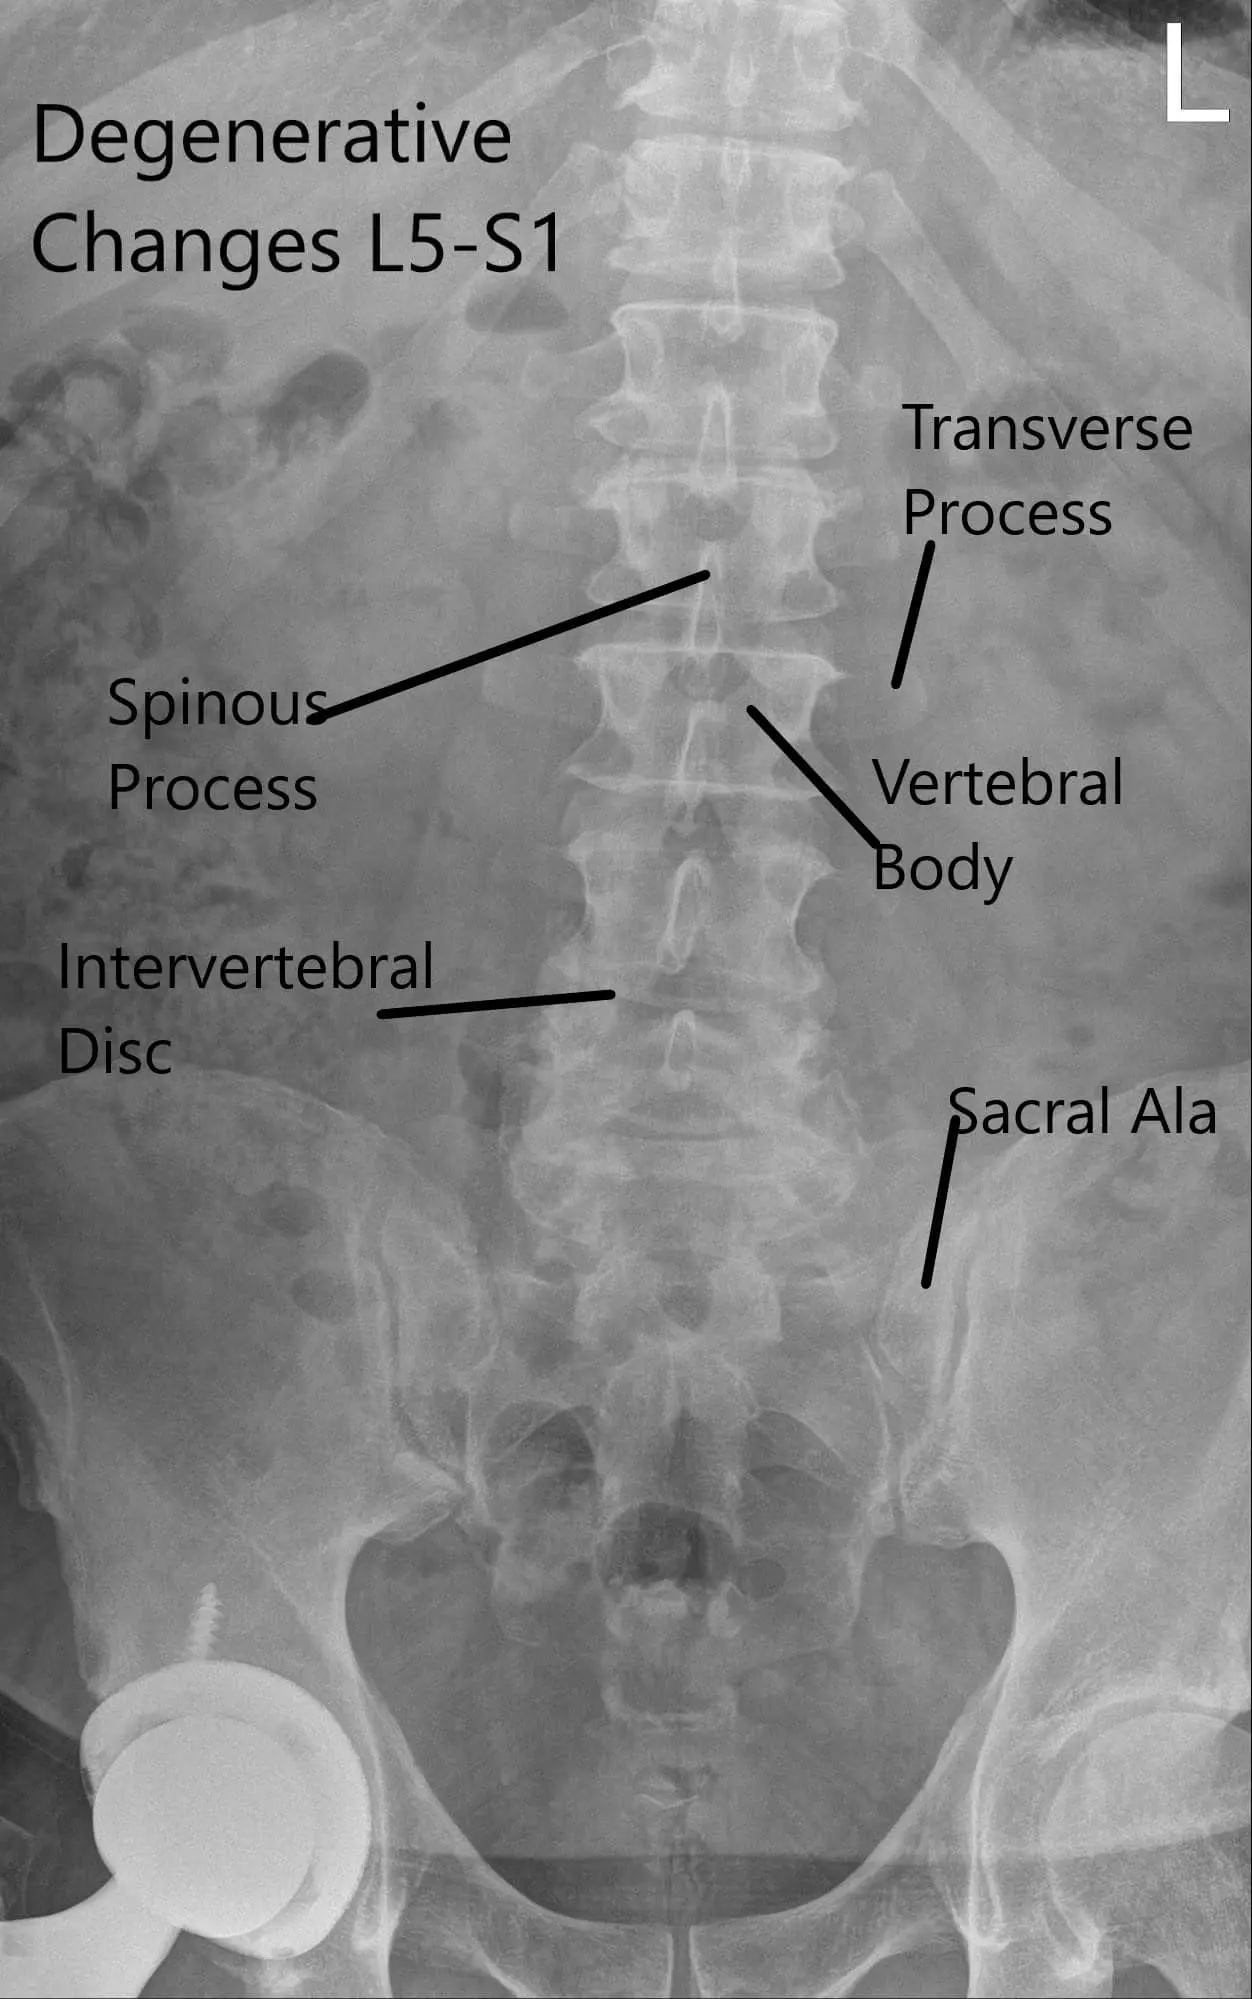

X-ray of the lumbar spine was reviewed with the patient. The X-ray revealed severe degenerative changes at L5-S1 and 5 mm anterolisthesis at L4-5.

Preoperative X-ray LS spine in AP and Lateral Views

Preoperative X-ray LS spine in AP and Lateral Views 2

Preoperative X-ray LS spine in AP and Lateral Views.